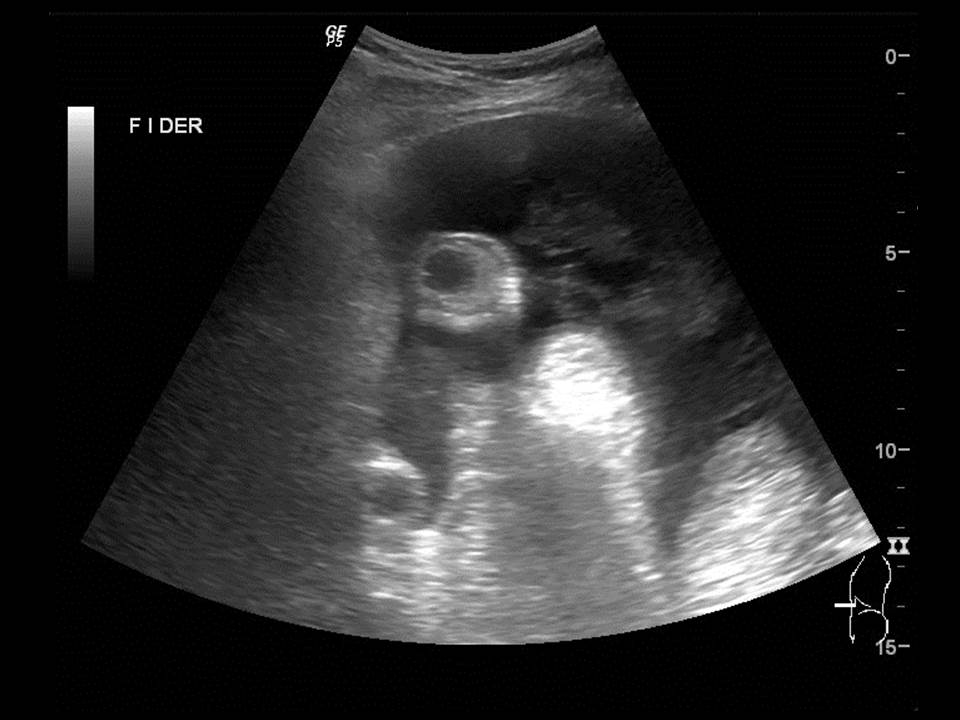

Paciente de 12 años con dolor abdominal. Remitida para estudio de masa intraabdominal.